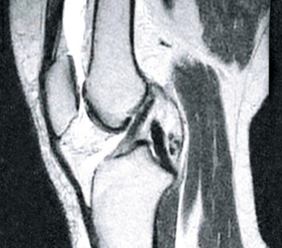

PRED

PO

Fotografia vľavo ukazuje prázdne miesta v kĺbovom puzdre, ktoré sú výsledkom nadmernej hydratácie tkaniva. Po ošetrení bola štruktúra synoviálnej tekutiny prestavaná (foto vpravo) a znovu získala svoju viskoelastickú konzistenciu a klzné vlastnosti. Kosti sú správne „namazané“, aby sa o seba neodierali, pretože sa obnovili tlmiace funkcie kĺbu.